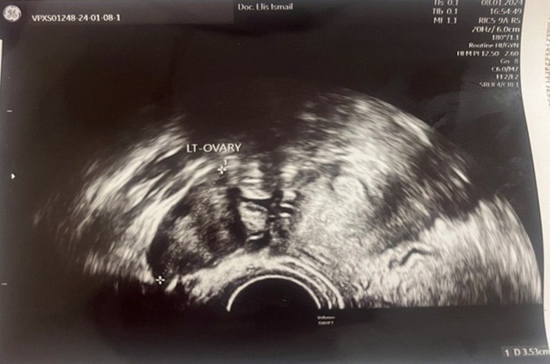

A 23-year-old asymptomatic female patient. During a routine gynecological examination, pelvic ultrasound identified a nonspecific tumor-like mass of solid consistency (Figures 1-3). The patient is sexually active and nulliparous. She has no history of abnormal menstrual bleeding or pelvic pain. Pelvic ultrasonography demonstrated a nonspecific tumor-like mass. The lesion was located in the vesicouterine space, anterior to the uterus (which was in anteversion and anteflexion with length 6.5 cm.) and posterior to the urinary bladder. The mass measured approximately 10 cm and had a predominantly solid component, with multilaminar hypoechoic bands within its capsule (Figures 1 and 4). Both ovaries were visualized and appeared normal on transvaginal ultrasonography (Figures 2 and 3). The pouch of Douglas is free of fluid.

Figure 2: TV-Ultrasonography image of left ovar-normal view.